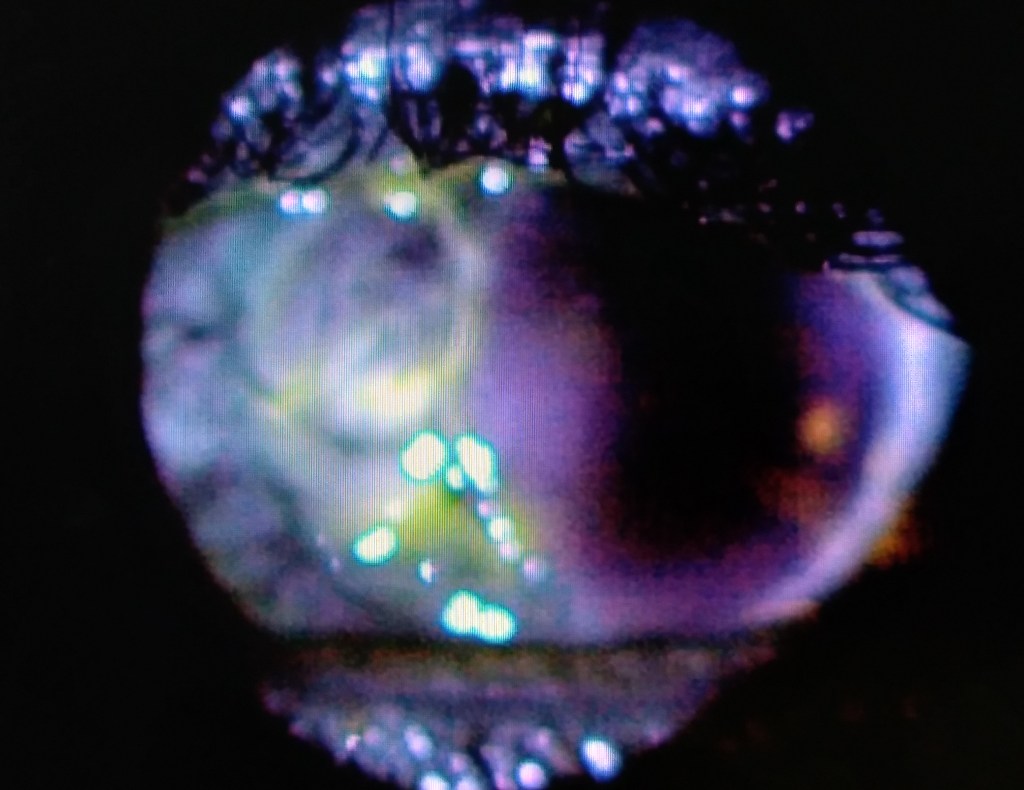

Pemeriksaan fisik

- Fluoresens test (menghitung ukuran defek/ulkus)/ Siedel test ( menentukan ada perforasi/tidak?)